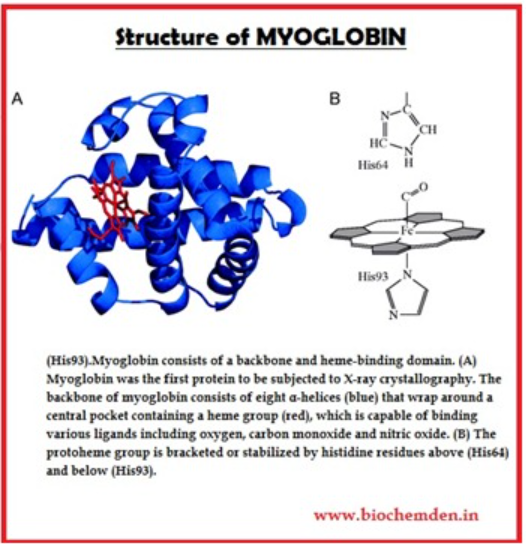

Heme | definition of heme by Medical dictionary

Heme binds and carries oxygen in the red blood cells, releasing it to tissues. Also spelled haeme. See also hemoglobin, porphobilinogen, protoporphyrin.

Heme | definition of heme

Heme | definition of heme OUTPUT formats

Heme | definition of Theme …. SCheme